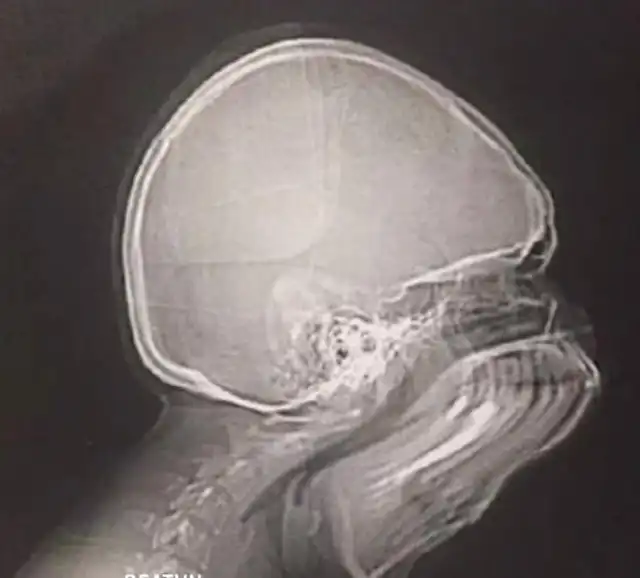

Да, это результат рентгена, во время которого пациент чихнул.